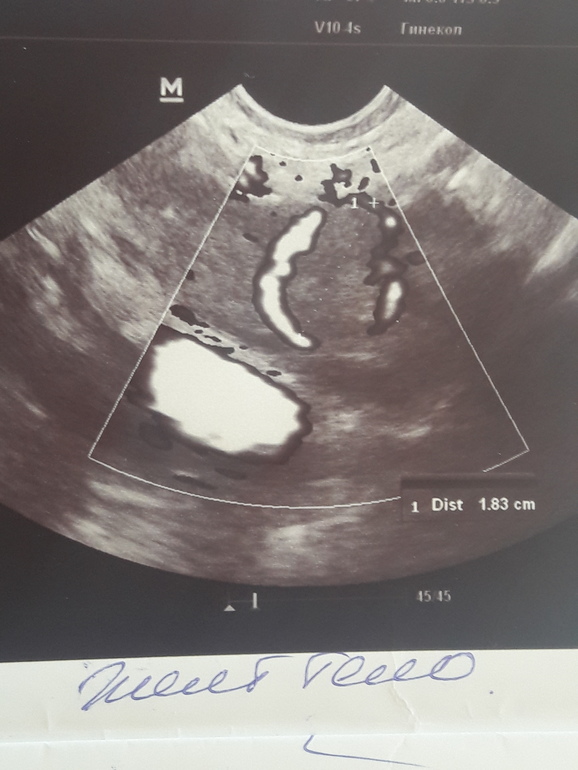

Девочки, кто разбирается в Узи? На что это похоже? Врач сама сомневалась, но поставила ановуляторный цикл. Хотя было наличие незначительного колличества жидкости..размер 27*20, узи на 16 дц, тест на овуляцию был положительным в обед на 13 дц..не могу успокоится, кажется уже второй цикл без овуляции..была лапара в августе (спкя).

Оно видите какое-на всех узи оно серое с какой то темноватой точкой внутри..а у вас оно черное

фолликул, так как жт серое с вкраплениями.

Узист сомневалась по причине того, что по тестам 16 дц это 1-2 дпо и возможно жт из фоллика еще не сформировалось, но краешки слишком ровные..так что решили что все таки не лопнул фоллик..